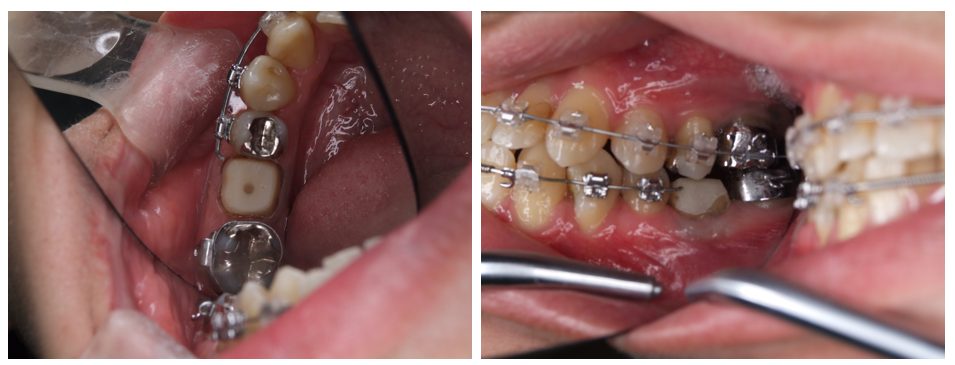

外科矯正治療・インプラント治療の症例紹介(三隅歯科クリニック)

三隅 賢祐(三隅歯科クリニック)

症例詳細

| 主訴 | 20代女性 矯正治療希望。治療途中の歯もあるので治したい。左顎関節が痛い。 |

| 治療内容 | 矯正治療を行いました。 |

| 治療費 | 1,400,000円(税込み) |

| 治療期間 | 3年(矯正治療期間 2年半) |

| 治療回数 | 40回 |

| 想定されたリスク | 顎骨の変形があったので、全身麻酔下による外科処置が必要になり、身体的、精神的負担が増す可能性がありました。 清掃状況によっては矯正中にむし歯が発生するリスクがありました。 |